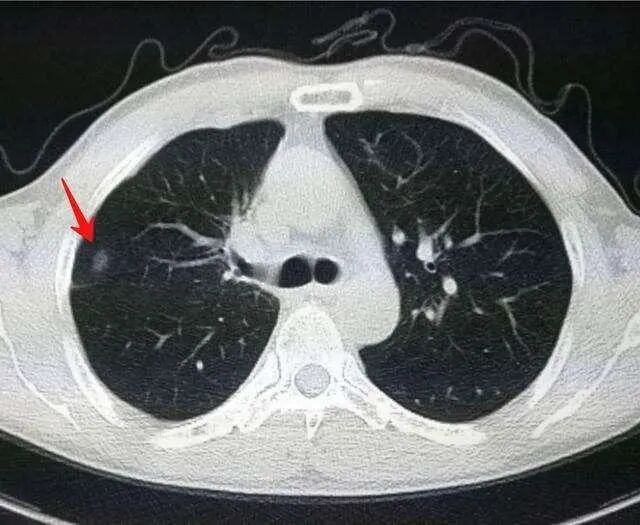

肺結(jié)節(jié)究竟是什么?所謂的肺結(jié)節(jié),就是做胸部 CT 檢查發(fā)現(xiàn)肺臟里的密度增高的結(jié)節(jié)(小于 3 厘米)。 胸部 CT:紅色箭頭所指為肺結(jié)節(jié)(黑的是肺,白的是結(jié)節(jié))